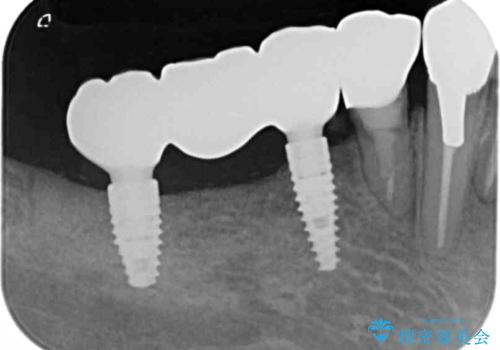

- インプラント治療を希望し数軒の医院で治療の相談をするも、骨の量が足りず治療が難しいと断られたのち当院にも相談にみえました。

長年の義歯の使用により骨の幅は非常に薄くインプラントを埋入するには大規模な骨の造成が必要な状態です。

インプラントを埋入するには十分な骨の量が必要で、吸収して少なくなってしまった場合でも造成できる場合があります。